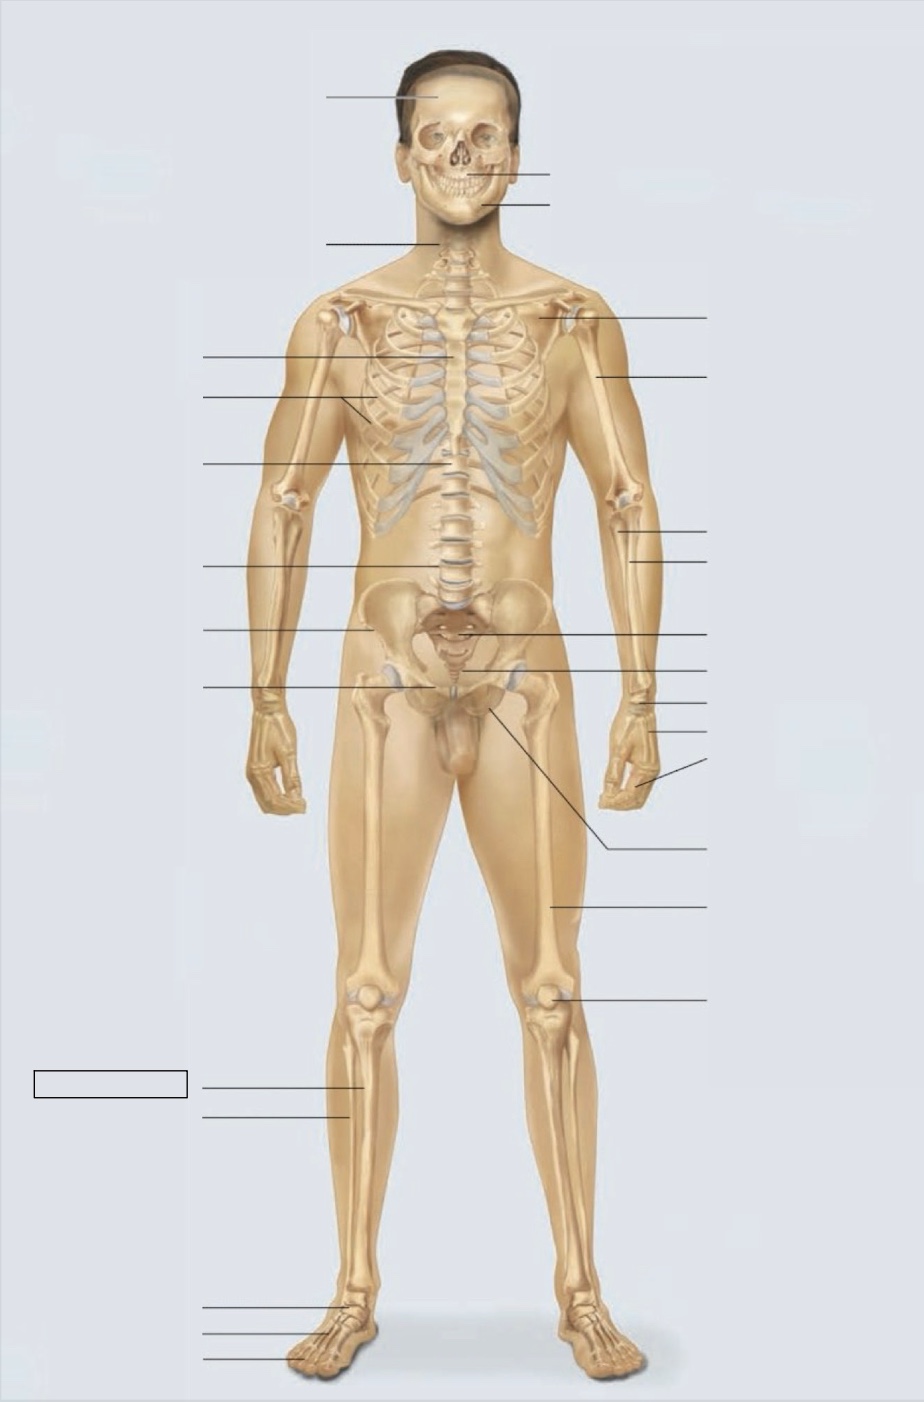

maxilla

mandible

scapula

humerus

ulna

radius

sacrum

coccyx

carpals

metacarpals

phalanges

ischium

femur

patella

phalanges

metatarsals

tarsals

fibula

tibia

pubis

ilium

lumbar vertebrae (L4)

thoracic vertebrae (T11)

ribs

sternum

cervical vertebrae

skull